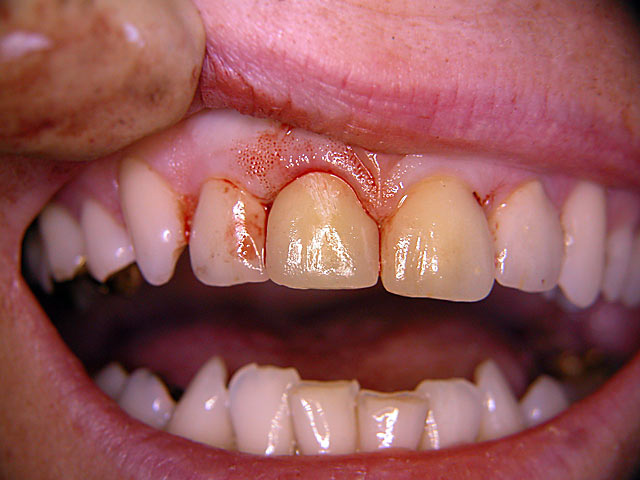

Frontzahn-Implantation: